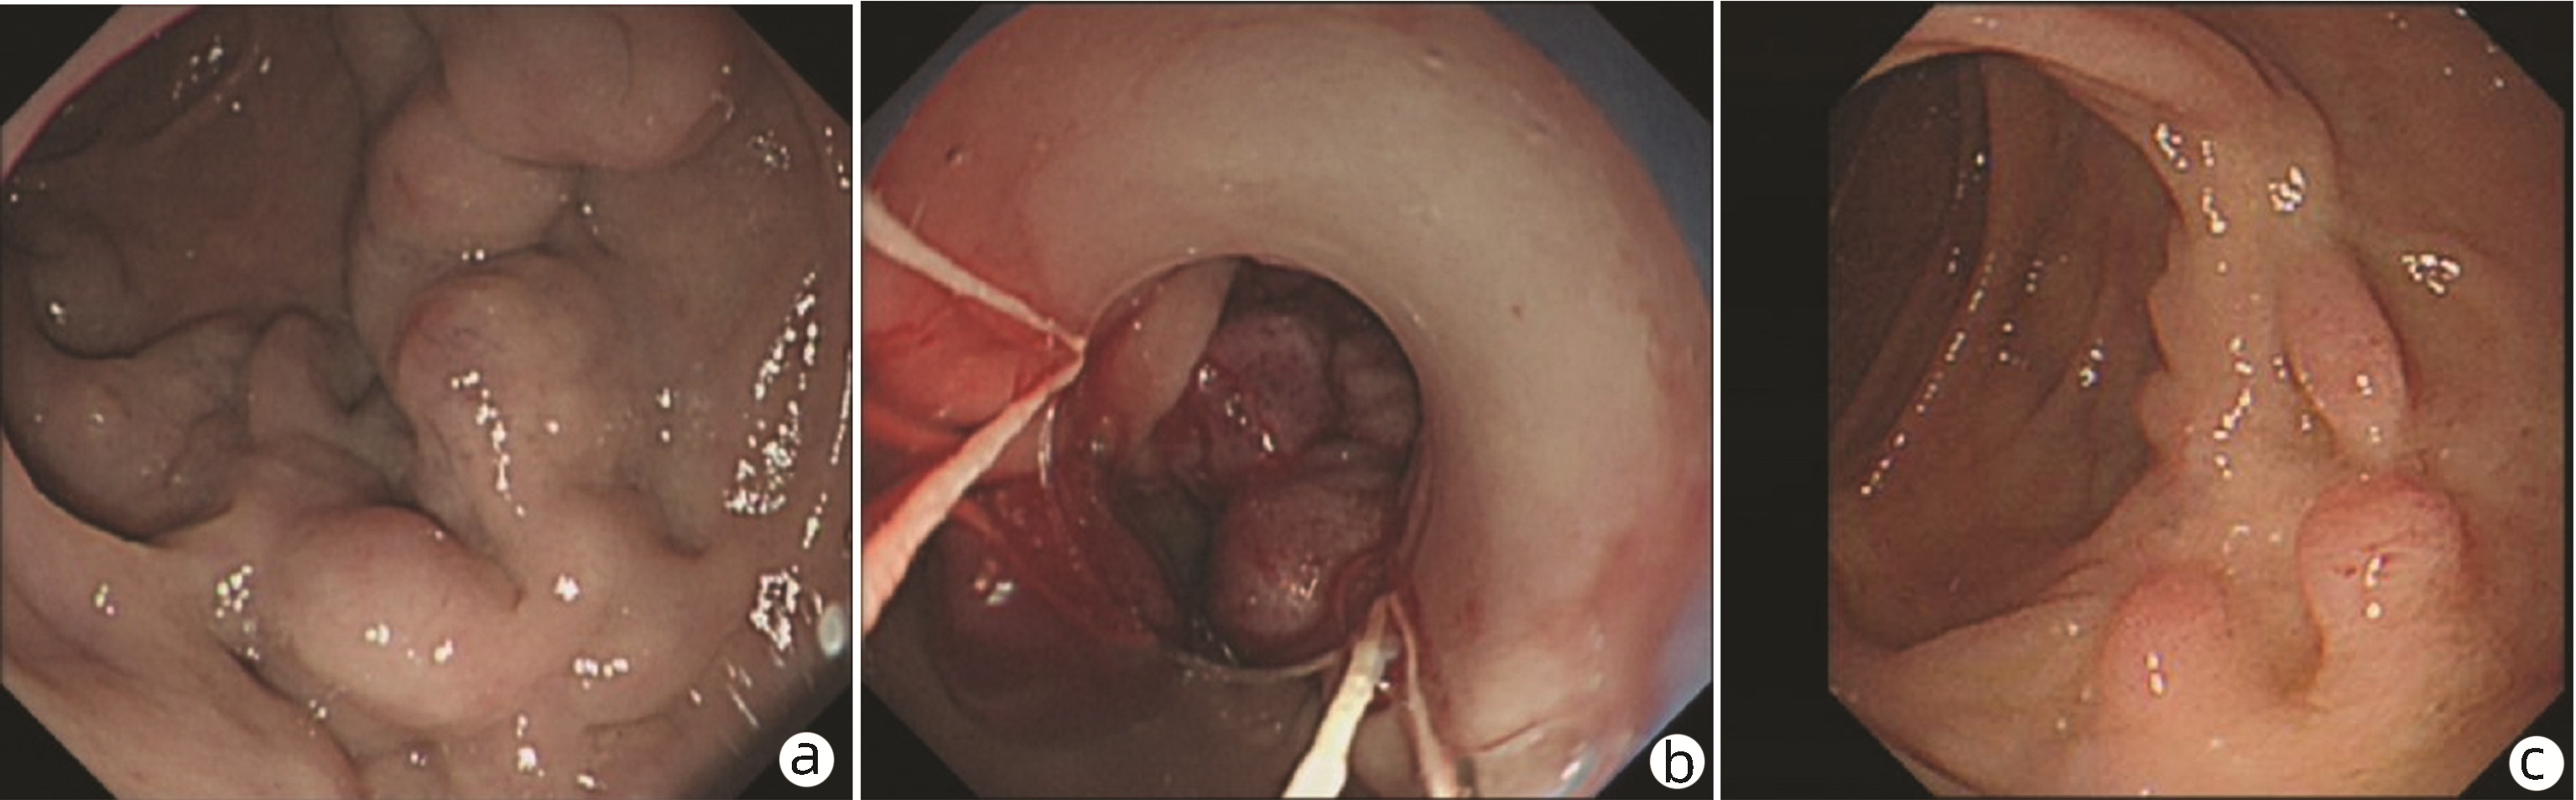

Clinical features of patients with portal hypertension due to Abernethy malformation: An analysis of 5 cases

Tingting BAI, Qin LI, Liangzhi WEN, Yanmei ZHANG, Yanling WEI, Bin WANG, Dongfeng CHEN, Hanyang XING

2023, 39(3): 620-625. DOI: 10.3969/j.issn.1001-5256.2023.03.020

Abstract(654) HTML (347) PDF (3579KB)(108)

Abstract: